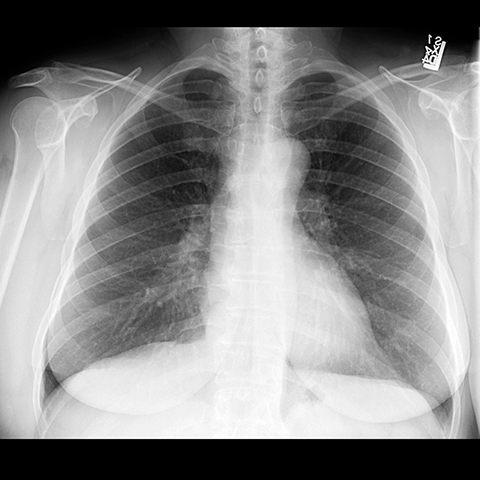

Radiographic Densities on CXR